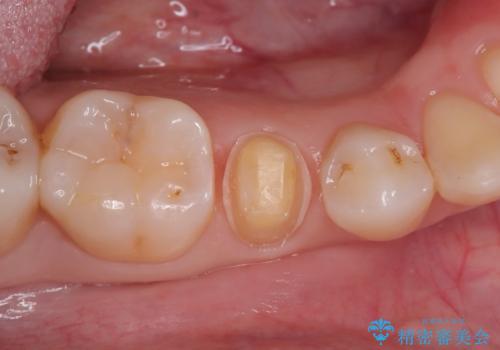

見落としやすい虫歯(コンタクトカリエス)を発見|精密診断で早期治療

- 患者様は特に痛みはなかったものの、定期検診で虫歯がないか確認したいとのことで来院されました。視診では明らかな虫歯は見当たりませんでしたが、レントゲン検査で歯と歯の間(コンタクトポイント)に虫歯(コンタクトカリエス)を発見。この部分の虫歯は初期では自覚症状が少なく、発見が遅れると治療範囲が広がることがあるため、早期に適切な治療を行う方針としました。

虫歯の部分のみを慎重に削除し、できる限り健康な歯質を残すように配慮しました。その後、強度があり適合性の高いセラミッククラウンを装着し、機能性と審美性の両方を確保。セラミックは変色しにくく、長期的な再発リスクも低減できるため、患者様にも安心していただけました。定期検診を継続することで、今後の虫歯リスクも管理していきます。